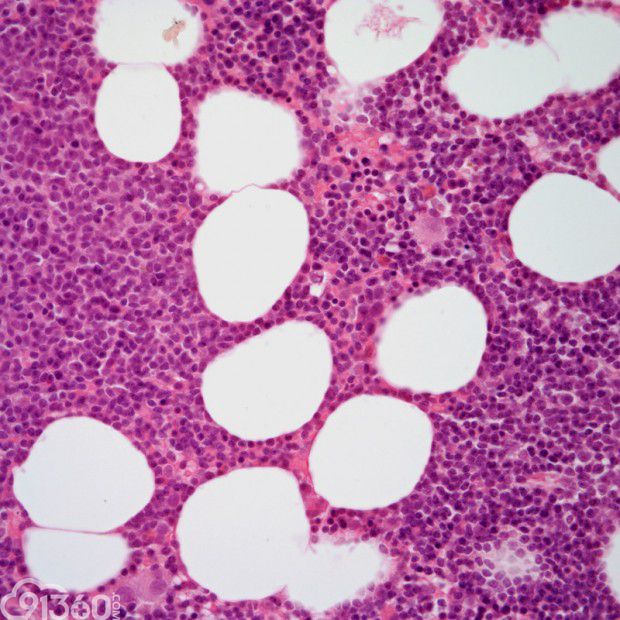

间变性大细胞淋巴瘤,ALK阳性 – 91360智慧病理网

ALK阳性间变性大细胞淋巴瘤 – 慧海拾穗博客 – 华夏病理网博客